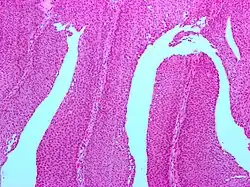

| Micrograph of a PUNLMP. Intermediate magnification. H&E stain. | |

Histologically, they have a papillary architecture with slender fibro vascular cores and rare basal mitoses. The papillae rarely fuse and uncommonly branch. Cytologically, they have uniform nuclear enlargement.